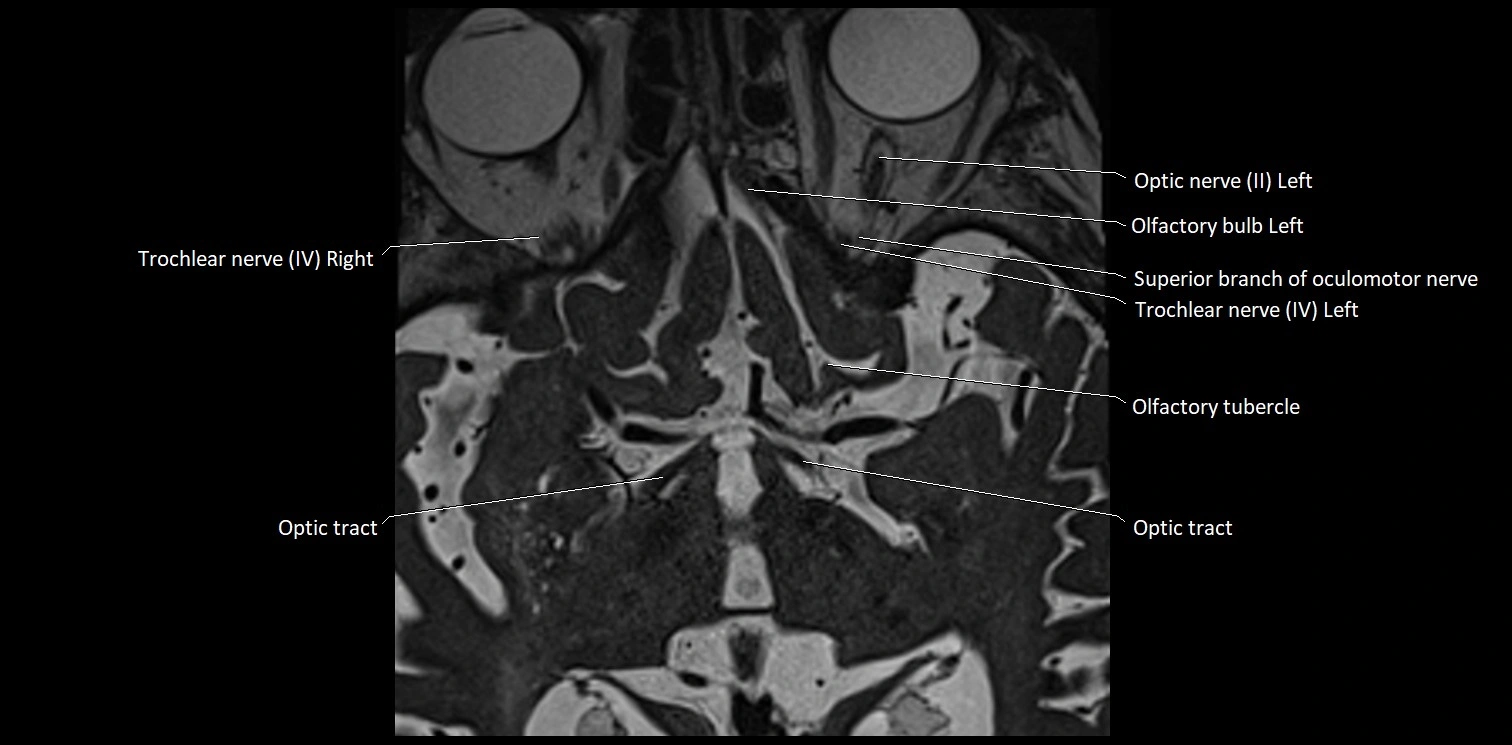

MRI images

image